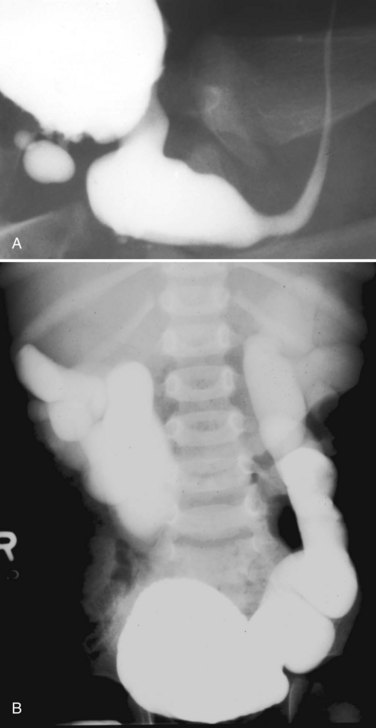

Young’s type I valves make up 95% of all posterior urethral obstructions (Fig. 126–2).

Figure 126–2 A, Voiding cystourethrogram demonstrates a typical type I posterior urethral valve with a dilated posterior urethra, elevated bladder neck, and valve leaflets obstructing the flow of contrast material from the bladder. B, This cystoscopic image from the distal urethra shows the valve leaflets forced into the lumen with the bladder full, illustrating their obstructive effect.